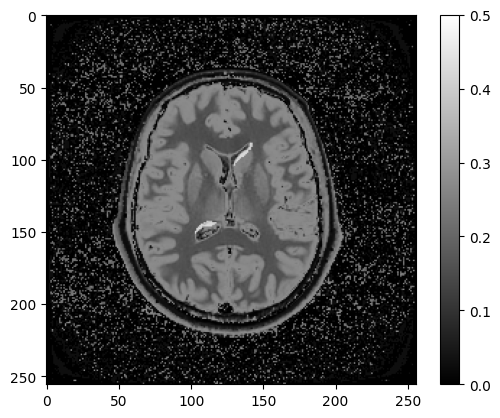

The correct answer was A - (TI = 3 s, TR = 10 s, TE = 150 ms, FA = 90 deg). Here’s what this FLAIR image looks like:

Figure 7.7:Inversion recovery image with TI = 3 s, TR = 10 s, TE = 150 ms, FA = 90 deg

Two periventricular lesions are clearly identifiable using this imaging protocol, which were hard to see on a regular T2w image Figure 7.2. The properly timed TI nulled the ventricular signal, whereas that long TR and TE provided sufficient T2 weighting to contrast against the nearby white matter, resulting in bright lesions, which are typically called hyperintese lesions.